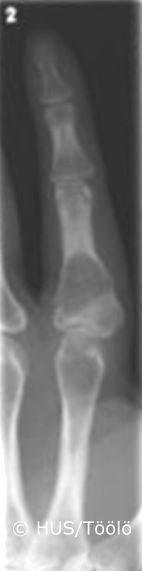

Kuva 1.

Enkondrooma sormessa. Enkondrooma vasemman etusormen tyvijäsenessä. Kondrooma on melko tavallinen hyvänlaatuinen rustoa muodostava luukasvain. Kun se sijaitsee kokonaan luun sisällä, siitä käytetään nimitystä enkondrooma. Se on usein oireeton ja todetaan silloin sattumalöydöksenä käden tai jalan röntgentutkimuksen yhteydessä.

Kuva: HUS/Töölö, Aarne Kivioja